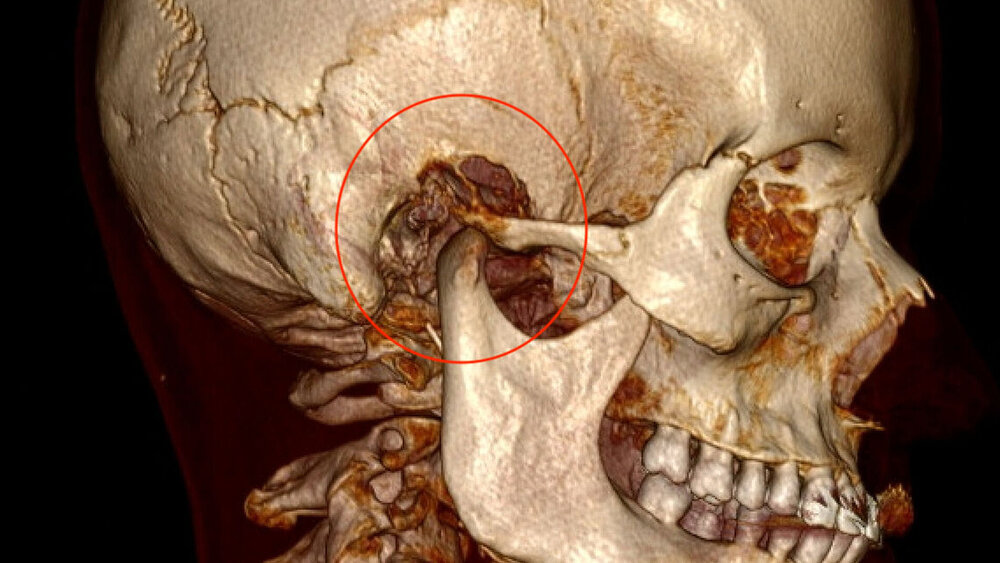

Zufallsbefund eines Riesenzelltumors bei langjähriger Bruxismus-Patientin